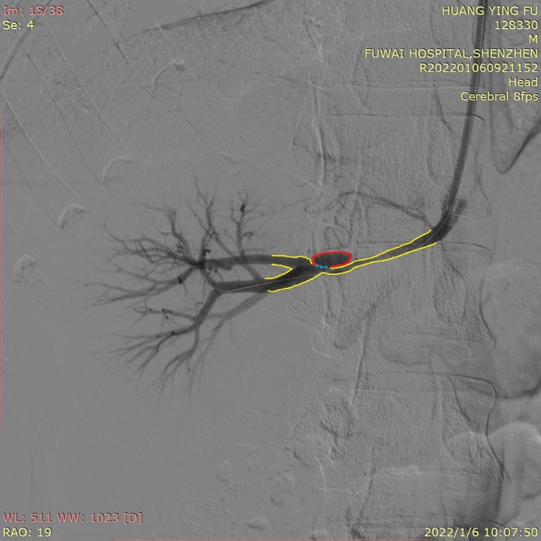

术中造影图像提示右肾动脉夹层,真腔已经压迫至一条细线了,如果不治疗,不仅血压血钾无法控制,右肾也会因缺血而萎缩、失去功能。

注明:红色圈圈是假腔,蓝色虚线是破口,黄色血管是真腔。

同时,由于这个破口临近肾动脉血管分叉,手术必须在封堵破口的同时,不能影响两个分支的血液供应,要求支架的定位必须非常精准。